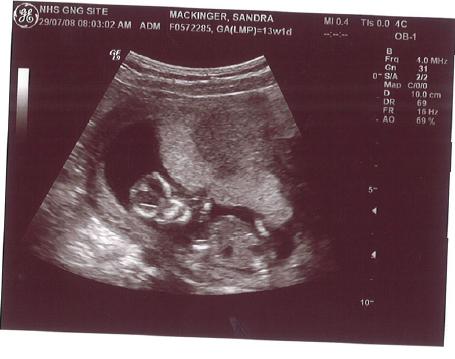

14. Schwangerschaftswoche:

Daumenlutschen! Das hat er eindeutig vom Papa!

Unser kleiner T-Rex ;-)